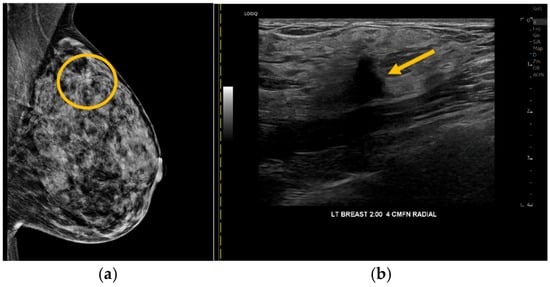

Improving Lesion Location Reproducibility in Handheld Breast Ultrasound

by James Chiu, Davide Bova, Georgia Spear, Jacob Ecanow, Alyssa Choate, Pierre Besson and Calin Caluser

Interoperator variability in the reproducibility of breast lesions found by handheld ultrasound (HHUS) can significantly interfere with clinical care. This study analyzed the features associated with breast mass position differences during HHUS. The ability of operators to reproduce the position of small masses [...] Read more.

Interoperator variability in the reproducibility of breast lesions found by handheld ultrasound (HHUS) can significantly interfere with clinical care. This study analyzed the features associated with breast mass position differences during HHUS. The ability of operators to reproduce the position of small masses and the time required to generate annotations with and without a computer-assisted scanning device (DEVICE) were also evaluated. This prospective study included 28 patients with 34 benign or probably benign small breast masses. Two operators generated manual and automated position annotations for each mass. The probe and body positions were systematically varied during scanning with the DEVICE, and the features describing mass movement were used in three logistic regression models trained to discriminate small from large breast mass displacements (cutoff: 10 mm). All models successfully discriminated small from large breast mass displacements (areas under the curve: 0.78 to 0.82). The interoperator localization precision was 6.6 ± 2.8 mm with DEVICE guidance and 19.9 ± 16.1 mm with manual annotations. Computer-assisted scanning reduced the time to annotate and reidentify a mass by 33 and 46 s on average, respectively. The results demonstrated that breast mass location reproducibility and exam efficiency improved by controlling operator actionable features with computer-assisted HHUS. Full article